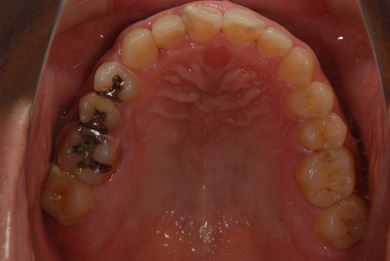

インプラントの症例写真 IMPLANT

抜歯即日スピードインプラント治療

| 性別/年齢 | 男性 / 38歳 | ||||||||||||||||||||||||||||||||

| 主訴 | 10年位前に虫歯治療をした右下奥歯のつめ物が取れ、再治療を受けた際にインプラントをすすめられたため、治療相談で来院。 | ||||||||||||||||||||||||||||||||

| 治療方針 | 抜歯と同時にインプラントを埋入し、治療期間を短縮する。 | ||||||||||||||||||||||||||||||||

| 治療内容 | インプラント1本(抜歯即日スピードインプラント)、ハイブリッドセラミッククラウン1本 | ||||||||||||||||||||||||||||||||

| 総治療費 | 257,250円 | ||||||||||||||||||||||||||||||||

| 治療期間 | 6ヶ月 |